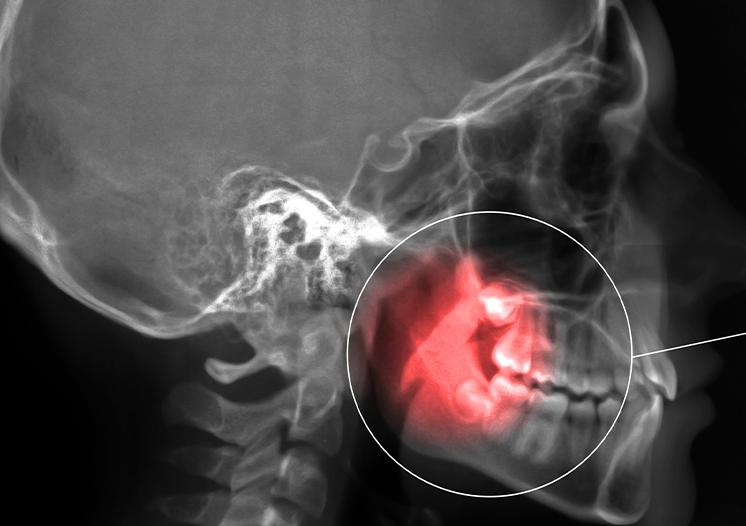

When there is not enough space for the wisdom teeth to erupt at all, they can cause pain in the gums and bone as they shift. This is known as ‘Impacted Wisdom Teeth.’ When your wisdom teeth are impacted, the opening around the teeth may become a fertile ground for bacteria to start developing and may lead to an infection in the gum tissues. As a result of this infection, you may experience discomfort, swelling, pain, and illness. The early removal of impacted wisdom teeth is often recommended to avoid future problems and to avoid costly surgical procedures.

Dr. Struan Vaughan and Dr. Matt Cosman will complete a thorough examination of your mouth, including x-rays that will help diagnose the type of wisdom teeth removal you require. Regular dental exams also help you keep your gums and teeth healthy, allowing us to identify any potential concerns to prevent costly dental procedures down the road.

If your wisdom teeth are aligned properly, and the surrounding gum tissue is healthy, wisdom teeth do not always have to be removed. With our clinical exam and panoramic imaging, we can inform you if you or your child’s wisdom teeth require extraction.